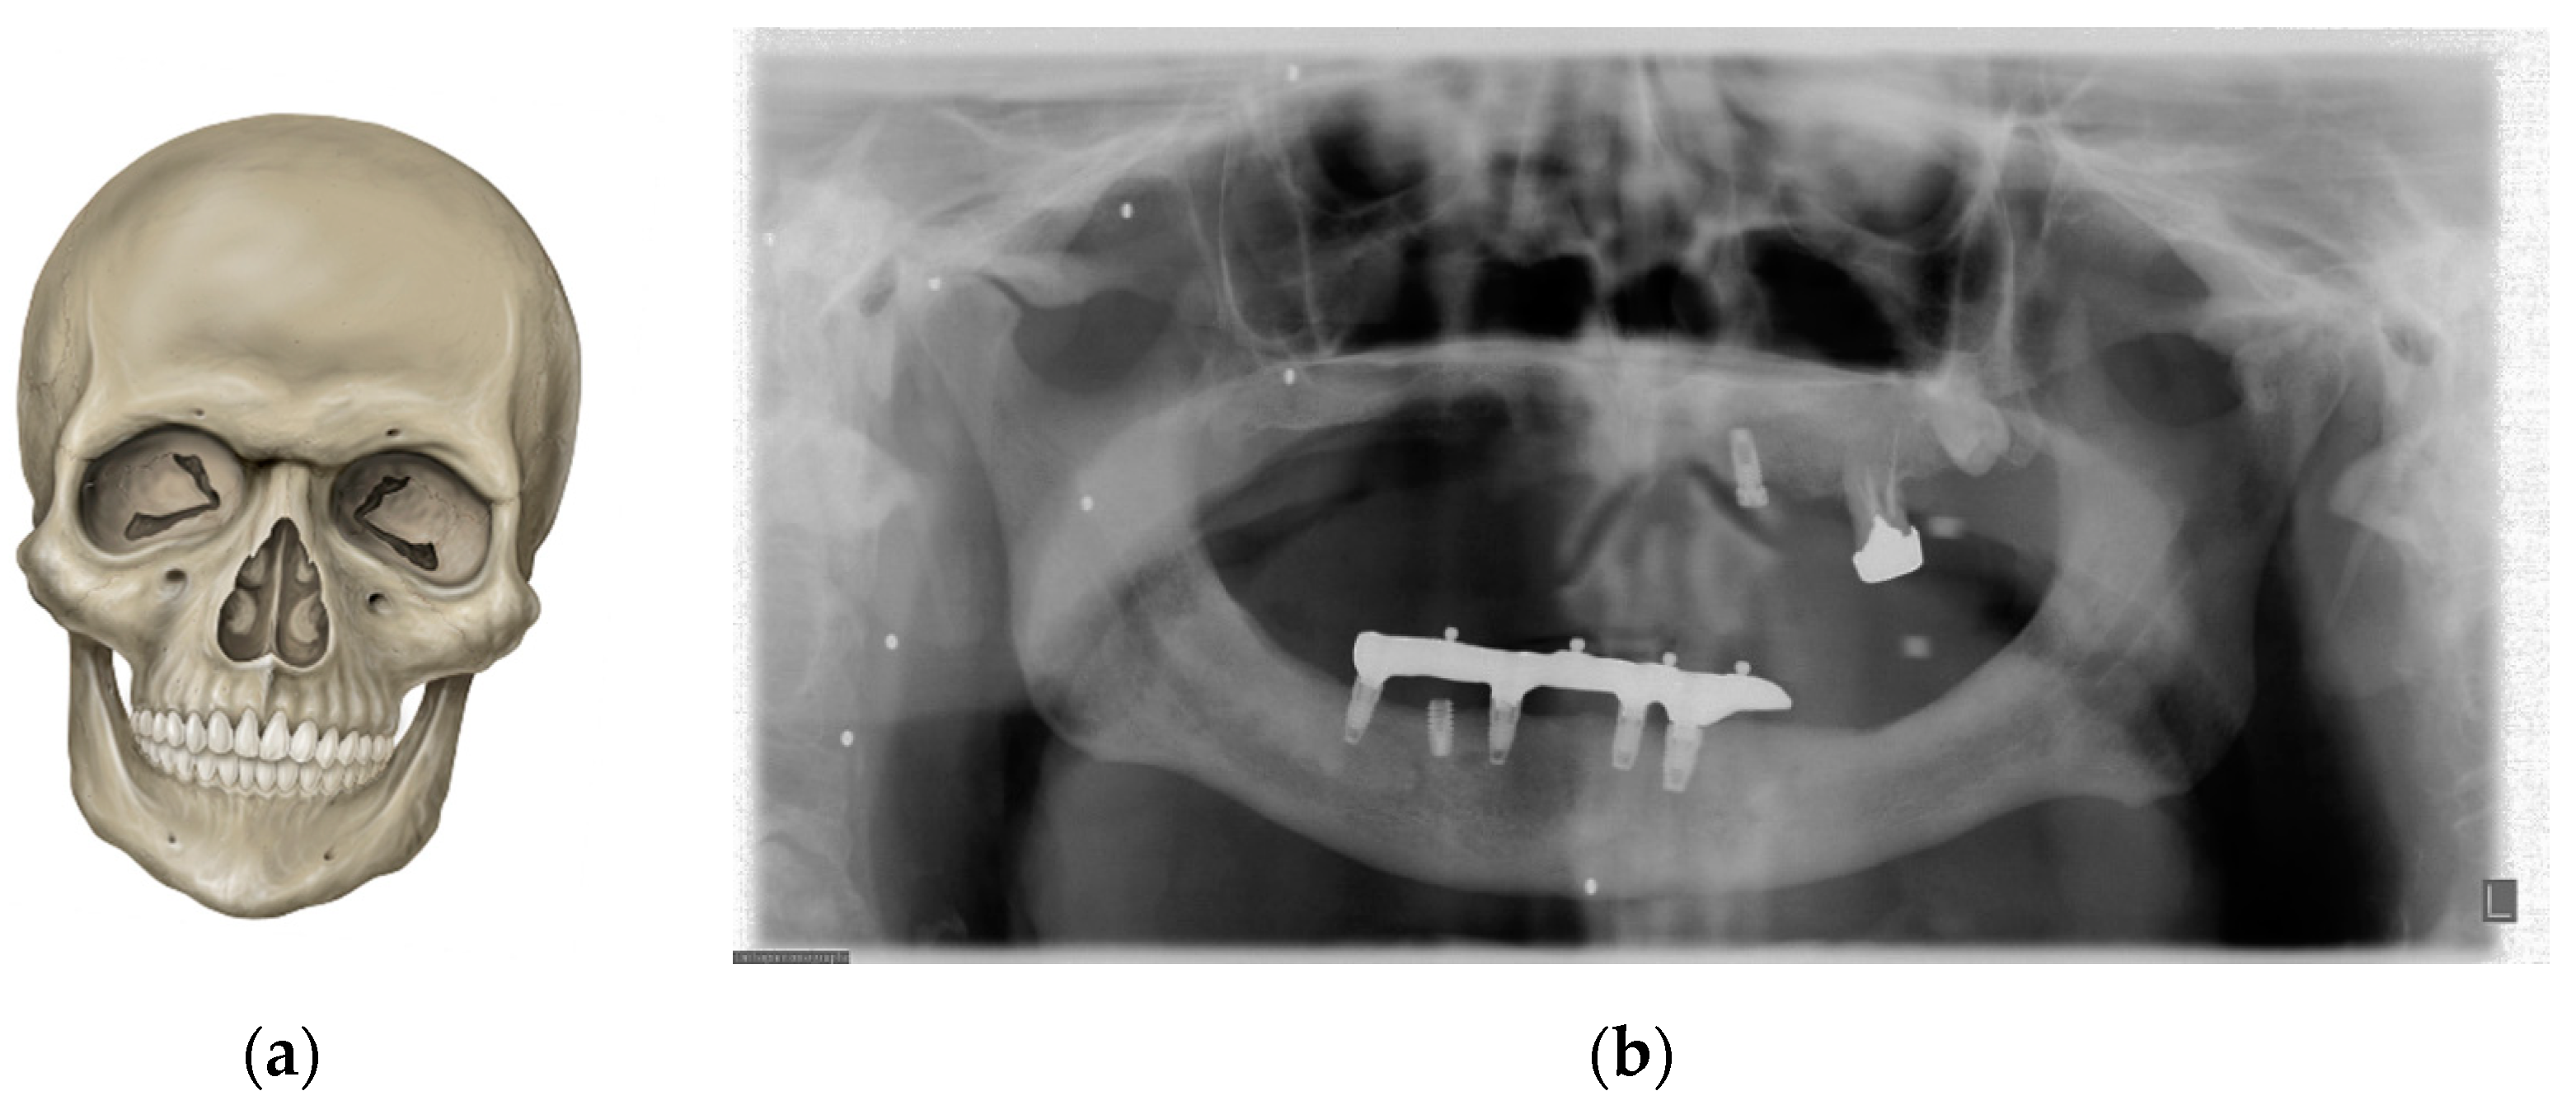

7. Metal and Motion Artefacts